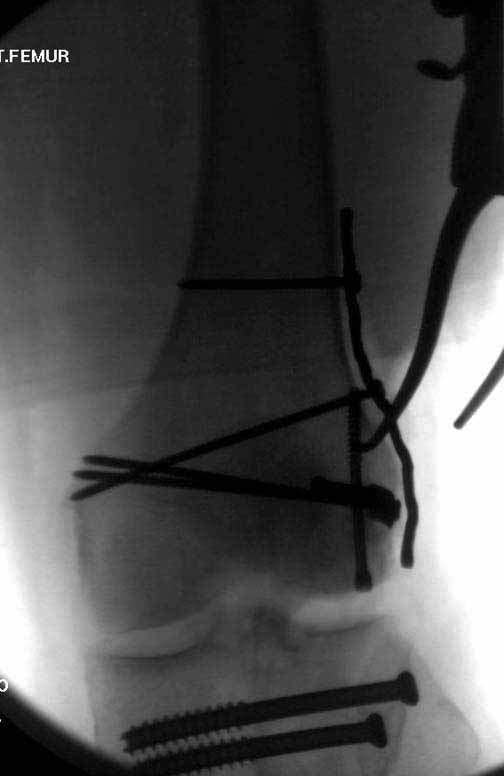

В приложении пример недавней операции, C3, открытая репозиция, фиксация мыщелков спицами и винтами, ретроградный синтез большеберцовым гвоздем 10,5 мм диаметром, винты 5 мм.

Такое проведение винтов становятся критически важным при переломах типа C3. Где, как правило, без открытой репозиции не обойтись. И пластины тут предлагают больше возможностей - и винтов много, и полиаксиально можно вводить. Иногда гвозди тоже получается использовать. Раз уж колено открыли, то через него и ввести проще, и винты в разных плоскостях с кондуктором удобнее вводить. Так что ретроградные становятся привлекательнее. И большеберцовые, кстати, в качестве ретроградных бедренных очень хорошо использовать.

Рационально ориентироваться на качественный аспект - проблема или решается, или нет. Переломы типа 33C1 или C2 (то есть без фронтального раскалывания мыщелков, как на показанной Вами томограмме) при обычном качестве кости успешно можно фиксировать гвоздями с фронтальными винтами. Получается, их прочностных характеристик уже достаточно.